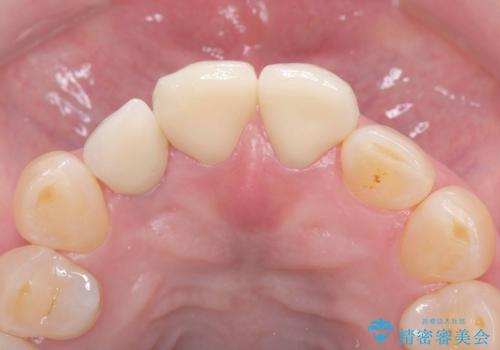

そのため今回は、右上2番を抜歯し、右上1番および左上1番をオールセラミッククラウンで審美的に修復しました。

治療期間も短く、抜歯からわずか3か月でオールセラミッククラウンを装着することができます。

また、オペ当日には仮歯まで装着するため、見た目を気にせず普段通りの生活を送ることができます。